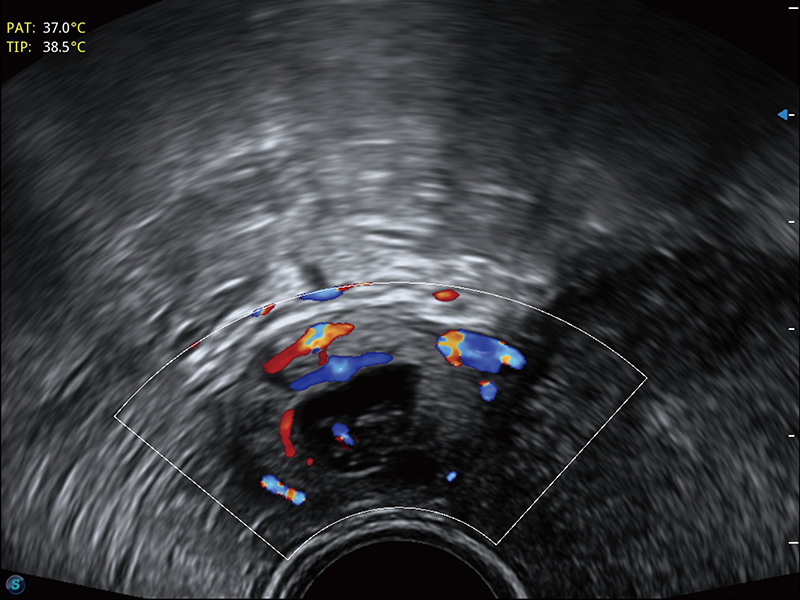

“生育问题”即关系民族复兴,也关系亿万家庭的幸福。随着婚育年龄推迟、社会压力增加等因素,越来越多人群也面临着“生不出、生不好”的问题。辅助生殖作为治疗不孕不育最有效的方法之一,也逐渐成为育儿新希望。而超声检查能为生殖需求人群的初诊评估提供宝贵的信息。 P20 Elite是开立医疗匠心打造的一款生殖应用型彩超。她继承开立医疗高端极光平台,突破性地将多款新型芯片及硬件模块进行整合,均衡了高端系统性能与小巧灵动机身。P20 Elite卓越的图像质量搭载专科探头,旨在为您提供全面的辅助生殖解决方案。

P20 Elite配备了丰富的生殖探头群和临床应用功能,在卵泡监测、穿刺取卵、胚胎移植、妊娠确认等领域,为生殖需求人群提供了新的临床机会,重新定义高端超声如何应用于生殖健康检查。